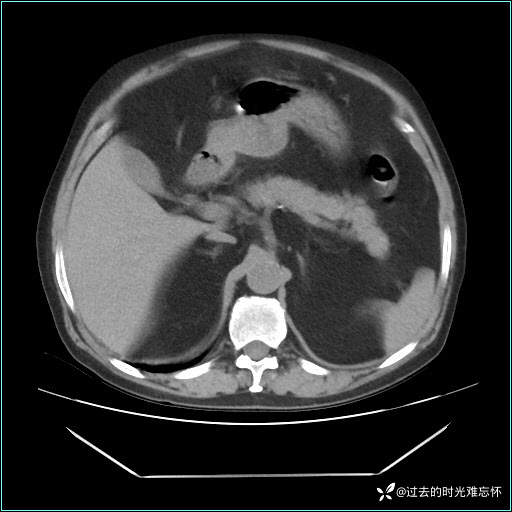

男子肚子大如孕晚期,一看腹腔竟被脂肪填满了...

患者男,71 岁,因「反复腹痛腹胀 1 月」入院。

现病史:患者 1 月前无明显诱因下出现腹痛腹胀症状,腹痛呈隐痛,当时未予以重视,后症状有所加重,常在进食辛辣刺激油腻等食物后出现腹痛,口服药物治疗症状能得到控制,病情控制一般。现为求诊治来我院,拟“腹痛”入院。病程中患者神志清楚,精神一般,无咳嗽咳痰,无恶心呕吐,近期体重无明显变化。